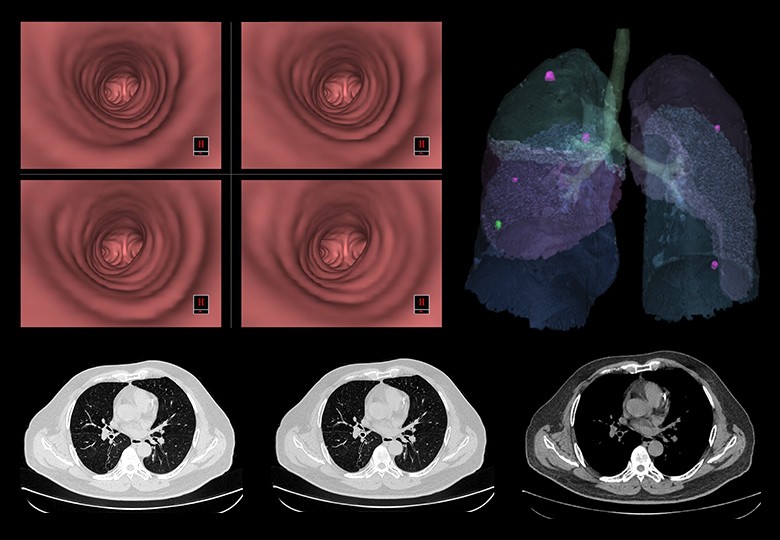

Album d'images cliniques

• Poumon